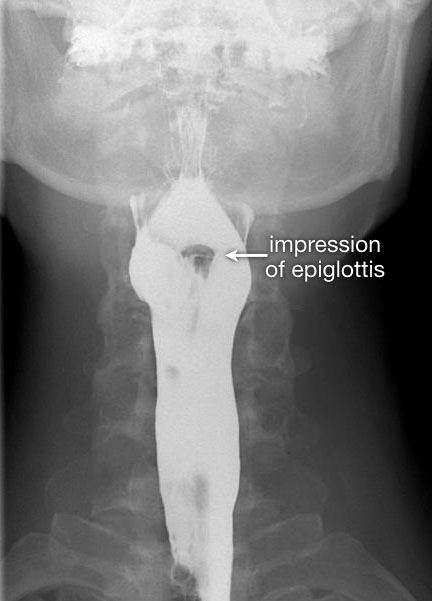

Tư thế thẳng (AP-view) quan trọng để đánh giá sự bất đối xứng.

Sau khi hoàn thành chuỗi hình ảnh giai đoạn hầu họng, cần theo dõi bolus thuốc cản quang toàn bộ đường đi xuống đến chỗ nối thực quản-dạ dày.